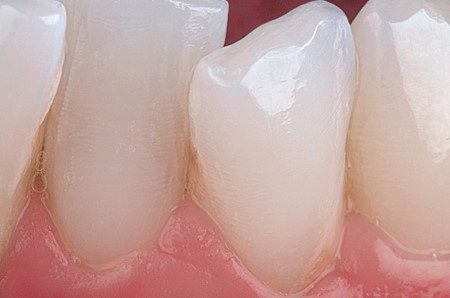

Hình 23. Sâu răng ở mặt gần R32, trước điều trị.

Hình 24. So màu được thực hiện trước khi đặt đê cao su.